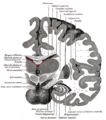

| رسم توضيحي لمسار ألياف lemniscus; medial lemniscus بالأزرق, lateral بالأحمر. | ||